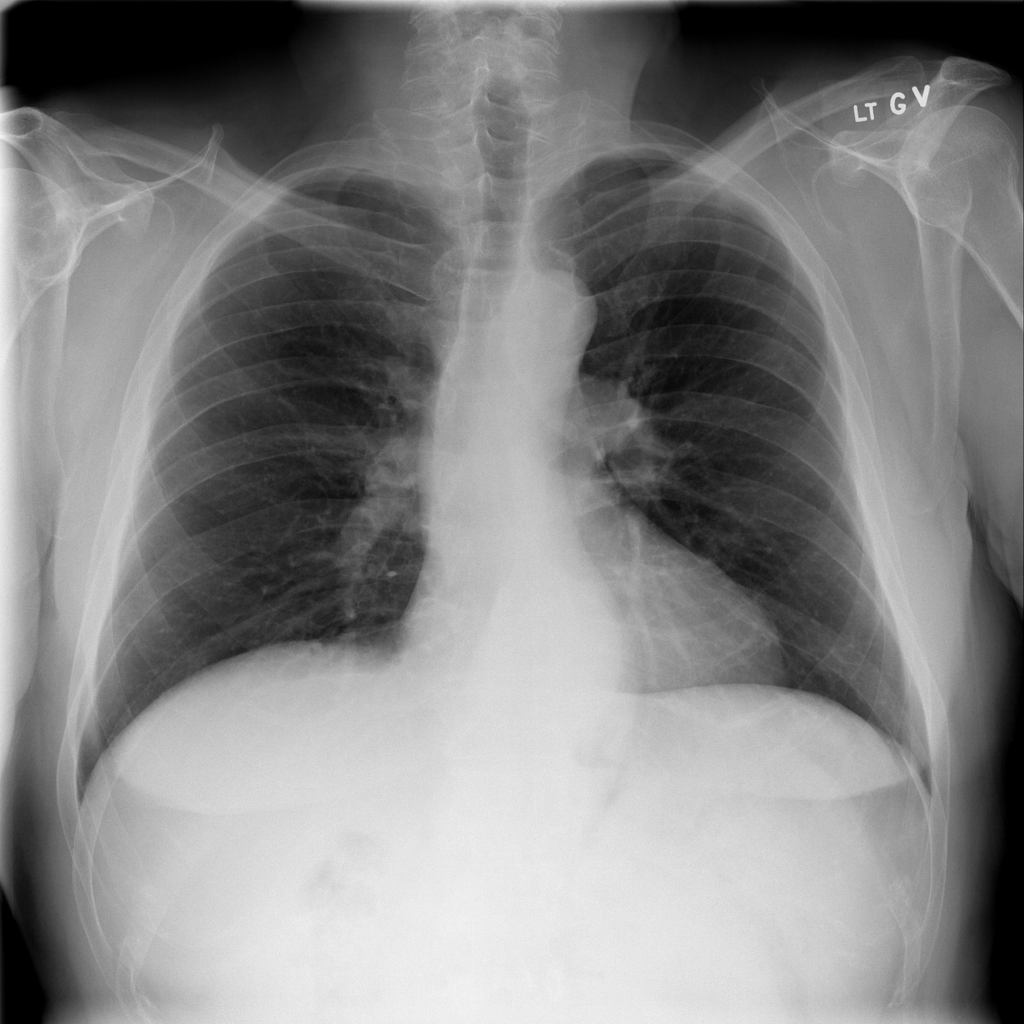

PAT-4F7E · IMG-000Hernia

PAT-4F7E · IMG-000

PA